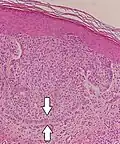

Палисады при базально-клеточной карциномые- Палисадные структуры при шваноме

Близким термином к розетке является палисад. Палисады обычно более протяжены, образуют своеобразный «забор» вокруг гнезда опухолевых клеток. Встречается в нейральных опухолях таких как шванома[8] или амелобластома. Также палисады можно увидеть в узловом варианте базально-клеточной карциномы.[9][10]

Псевдопалисады это зоны повышенной клеточности, которые окружают очаг некроза опухолевой ткани. Это часто свидетельствует о высокой степени злокачественности опухоли.[8] Часто встречается в глиобластомах.